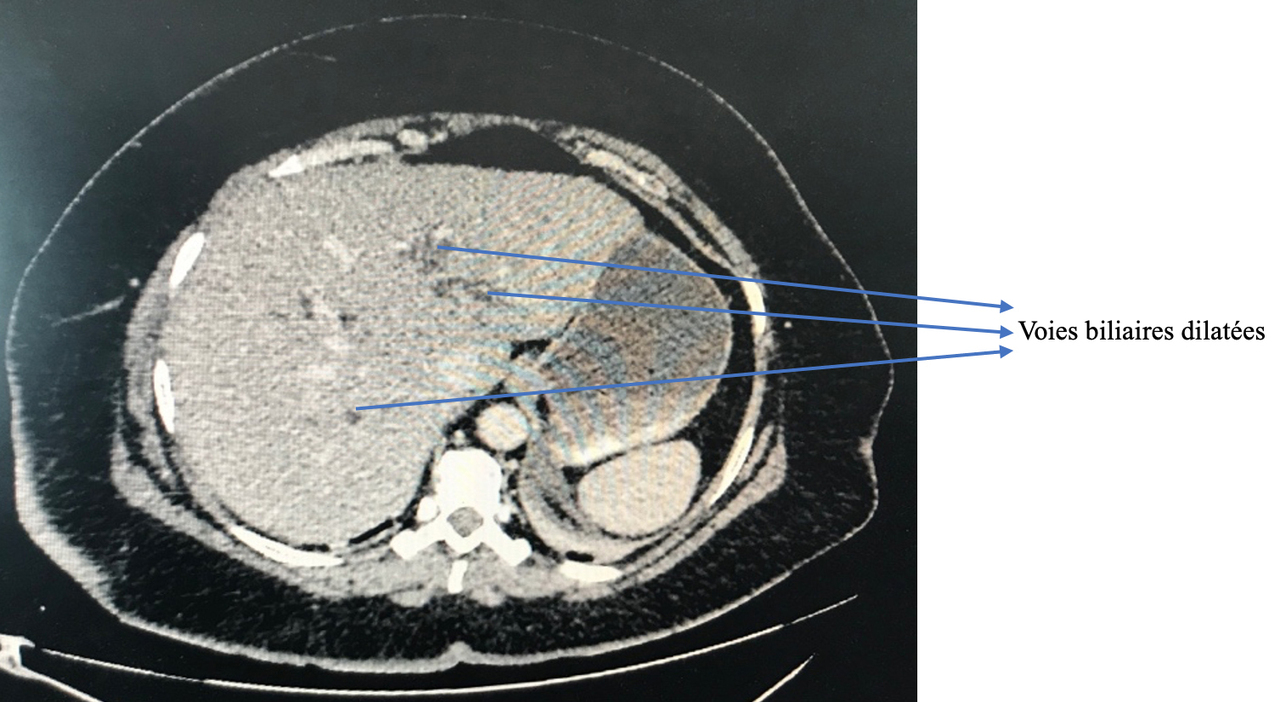

La douleur de la pancréatite est épigastrique irradiant dans le dos, majorée par la respiration profonde et la position antalgique est en chien de fusil.